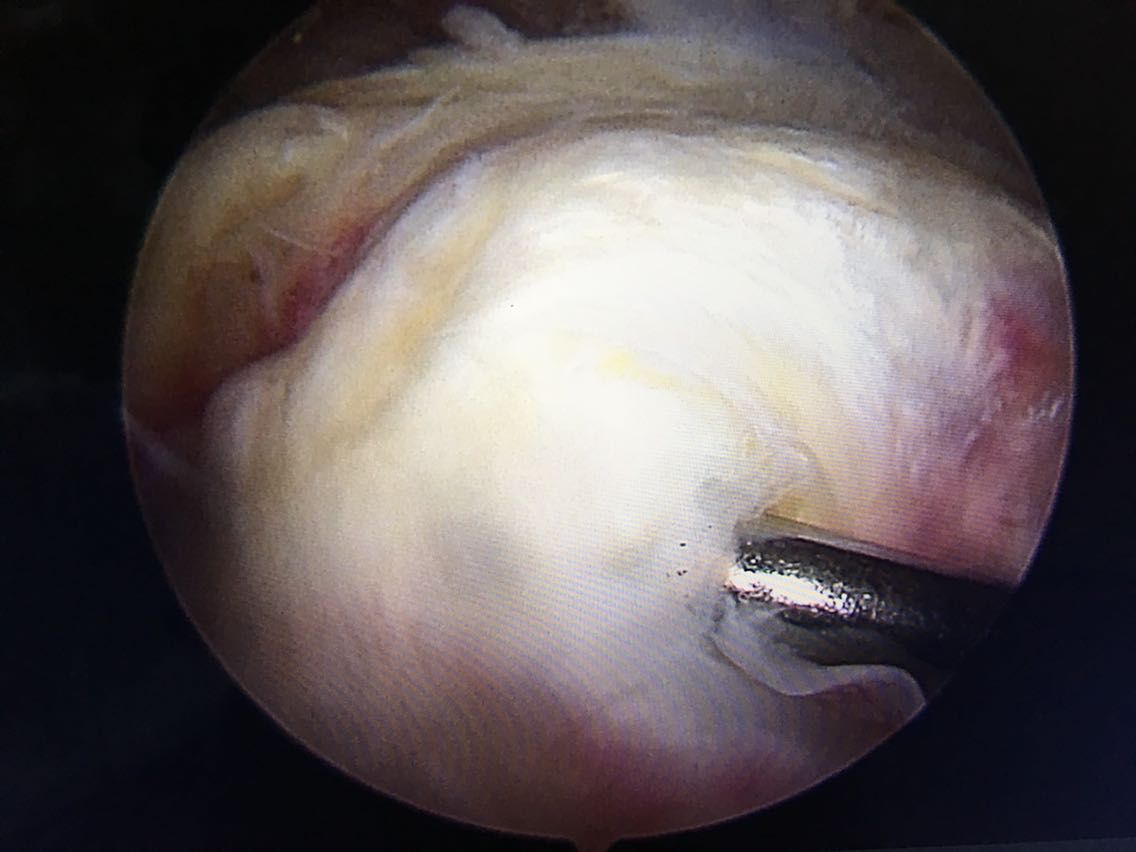

主诉:右肩关节疼痛、功能障碍6个月 现病史:患者于6个月前出现肩关节疼痛,以夜间明显,在当地医院诊断为肩周炎,给予指导关节功能锻炼,疼痛症状和功能障碍加重,效果不佳,来院就诊,核磁共振检查后,诊断为:肩袖撕裂 肩峰撞击症。收入院行关节镜下清理 肩峰成形 肩袖撕裂修补手术。

诊断:右肩袖撕裂 肩峰撞击症 冻结肩 治疗:关节镜下清理 肩峰撞击成形 肩袖撕裂修补手术。